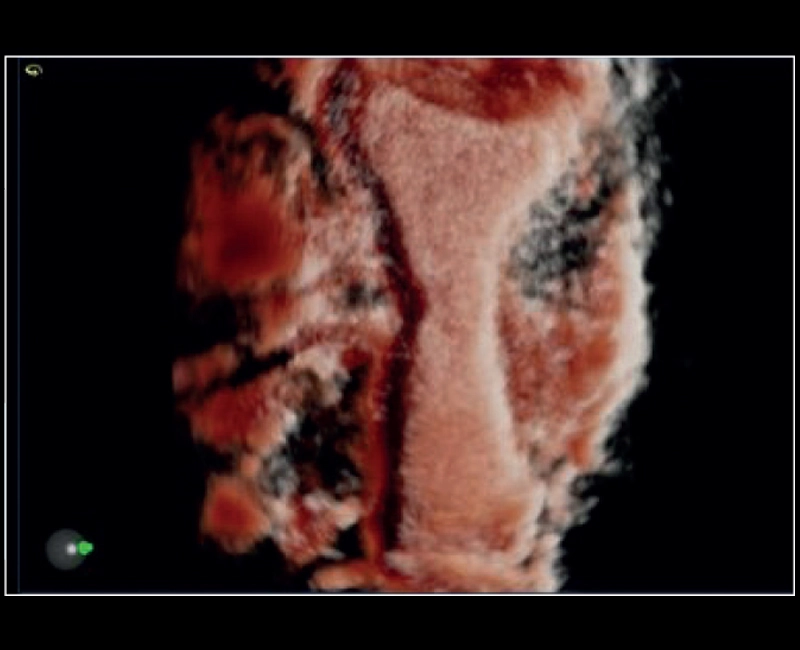

MyLab™E80 - 3D - Baby Face

MyLab™E80 - 3D - Baby Face

MyLab™9 Platform - Real-time baby face with 4D imaging

MyLab™9 Platform - Real-time baby face with 4D imaging

MyLab™9 Platform - Baby Face rendering in real-time with XLight

MyLab™9 Platform - Baby Face rendering in real-time with XLight